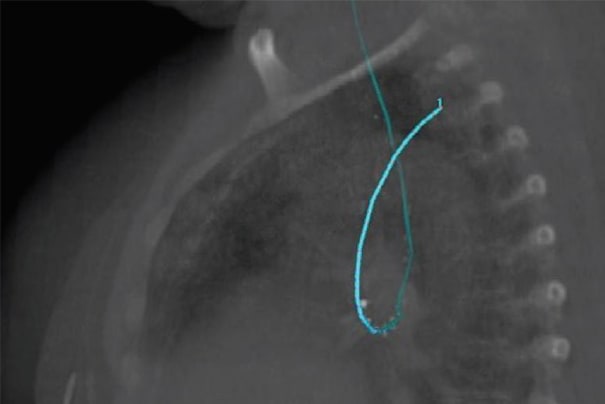

针对肺癌、小细胞肺癌及其他管腔内近距离治疗应用,医科达提供了两种先进的施源器。LumenCare®Azure施源器专门设计用于帮助放疗医师更好地实施肺癌和食道癌近距离治疗,扩大可治疗范围。

LumenCare Azure施源器套件为临床医生提供了肺癌近距离治疗应用的卓越解决方案。该套件专门设计用于更好地实施肺癌治疗,扩大可治疗范围。

LumenCare®施源器——图片由UZL Gasthuisberg(比利时鲁汶)提供